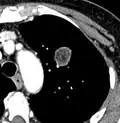

PET scan

If there is an intermediate risk of malignancy, further imaging with positron emission tomography (PET scan) is appropriate (if available). It can be done simultaneously as a CT scan in the form of PET-CT. Around 95% of patients with a malignant nodule will have an abnormal PET scan, while around 78% of patients with a benign nodule will look normal on PET (this is the test sensitivity and specificity).[15] Thus, an abnormal PET scan will reliably pick up cancer, but several other types of nodules (inflammatory or infectious, for example) will also show up on a PET scan. If the nodule has a diameter of less than one centimeter, PET scans are often avoided because of an increased risk of falsely normal results.[15][16][17] Cancerous lesions usually have a high metabolism on PET, as demonstrated by their high uptake of FDG (a radioactive sugar).

-

PET-CT of a tuberculoma.